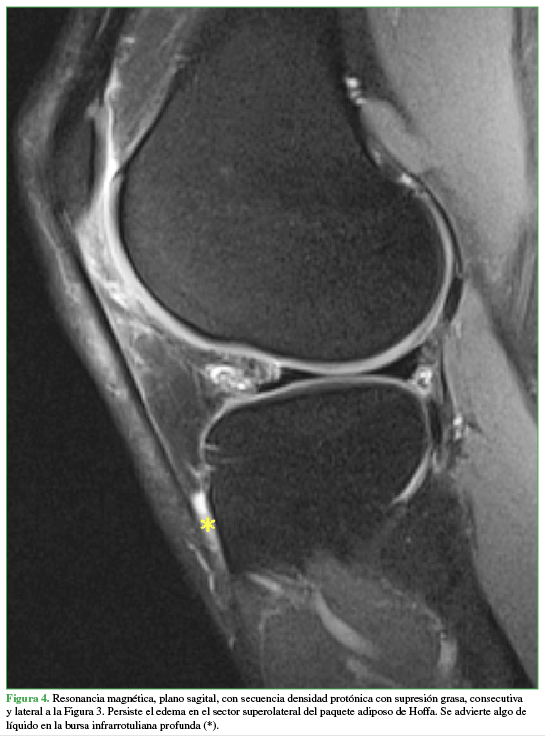

PropiaLuego se le realizó una resonancia magnética (RM) (Figuras 2,3,4,5,6) que mostró como hallazgo central la presencia de hiperintensidad en las secuencias líquido sensibles indicativa de edema en el sector superolateral del paquete adiposo infrarrotuliano (PAI) o de Hoffa. Se constató un desgarro degenerativo en el menisco externo y pequeños quistes parameniscales asociados, así como condromalacia rotuliana de bajo grado (imágenes no mostradas). Las estructuras óseas y ligamentarias eran de características normales.

Persiste el edema en el sector superolateral del paquete adiposo de Hoffa. Se advierte algo de líquido en la bursa infrarotuliana profunda(*).

Propia